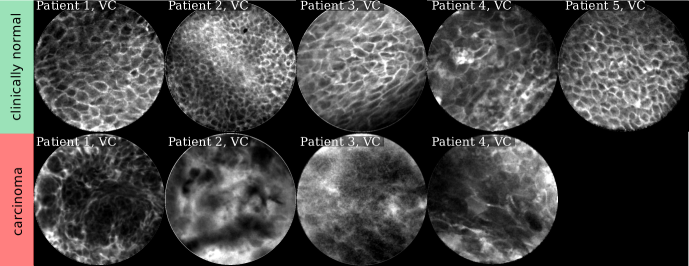

Refer to caption

Figure 2: Selected CLE Images acquired from the oral cavity (OC). First and third row show images from clinically normal regions, second and fourth row show images from lesion sites later diagnosed as OSCC.

Comparing the images in Figures 2 and 3, for clinically normal (and presumably healthy) tissue we find a large difference in contrast for some regions. While for images acquired from the alveolar ridge (rows 1 and 3, columns 5 - 6 in Fig. 2) and the vocal folds (top row in Fig. 3), contrast is generally good and cell outlines can be clearly spotted for most images, we find a much broader spread in image quality for images acquired at the hard palate and the lower inner labium (rows 1 and 3, columns 1-4 in Fig. 2).

In CLE images, the raw pixel value represents the optical (fluorescent) response to the laser light excitation. The optical receiver and analog to digital converter of the CLE scanner in use have a broad dynamic response. Thus, all images presented in this work and also in the CellVizio software are automatically compressed in their value range to fit the 8 bit gray level range of today’s screens and to increase contrast for the viewer. The median raw pixel value, however, is indicative of the amount of fluorescent light that was picked up by the scanner, and as such also related to the signal-to-noise-ratio of the image. We use median, as it is more robust to the (typically sparsely distributed) very bright areas representing micro-vessels filled with contrast agent, as e.g. in row 2, column 4 of Fig. 2. We evaluated the median raw pixel value on images for all anatomical regions separately (see Fig. 4). For images acquired from the hard palate and the lower inner labium, we find a significantly different distribution than for both other anatomical locations, in that the prevalence of images with low median value (and thus likely low SNR) is much higher for these regions. In contrast, the vocal fold and alveolar ridge area both have a rather low amount of noisy images. This underlines our visual observation derived from the representative images in Fig. 2.